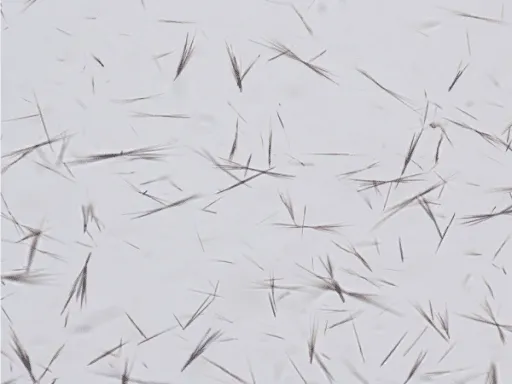

Gout belongs to a group of crystalline diseases occurring when uric acid crystals accumulate in joints and tissues. While deposits often cause no issues initially, the body may suddenly recognize them as foreign, triggering an intense inflammatory reaction. This manifests as a “gout attack” — often beginning overnight with excruciating pain, typically in the big toe, though other joints can be affected. The pain can be astronomical, leaping-out-of-your-skin kind of pain.